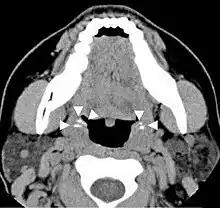

Diagnosis is usually made upon inspection. Tonsilloliths are difficult to diagnose in the absence of clear manifestations, and often constitute casual findings of routine radiological studies.

Imaging diagnostic techniques can identify a radiopaque mass that may be mistaken for foreign bodies, displaced teeth or calcified blood vessels. CT scan may reveal nonspecific calcified images in the tonsillar zone. The differential diagnosis must be established with acute and chronic tonsillitis, tonsillar hypertrophy, peritonsillar abscesses, foreign bodies, phlebolites, ectopic bone or cartilage, lymph nodes, granulomatous lesions or calcification of the stylohyoid ligament in the context of Eagle syndrome (elongated styloid process).[11]

Differential diagnosis of tonsilloliths includes foreign body, calcified granuloma, malignancy, an enlarged temporal styloid process or rarely, isolated bone which is usually derived from embryonic rests originating from the branchial arches.[12]